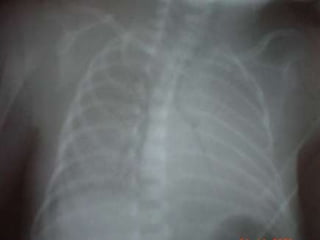

Radiología de Tórax: Clasificación BENCE: Grado I - II - III - IV:“Imagen en Vidrio Esmerilado”Laboratorio:AGA:   pH:    < 7.25            pCO2 > 40 mmHg.            pO2   < 60 mmHg

I. Radiografía de Tórax  < 7 espacios intercostalesDisminución de transparencia generalizadaPatrón retículo-granular uniforme  (vidrio esmerilado)Broncograma aéreoComplicacionesSd. de Fuga de Aire (aire entre pared torácica y parénquima pulmonar)Displasia broncopulmonar

ESTADIO I / FORMA LEVE:La imagen reticulogranular es muy fina.

El broncograma aéreo es muy discreto, no sobrepasa la imagen cardiotimica.

Membrana Hialina